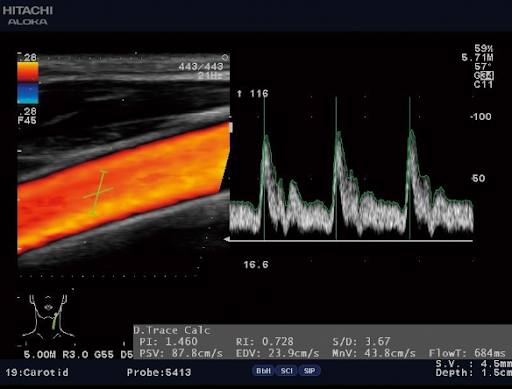

UST-5413 Линейный датчик 4-14 МГц / 38 мм / трапециевидное сканирование. Применение: малые поверхностные органы, периферические сосуды, вены конечностей, щитовидная железа, молочная железа, суставы, сухожилия, ортопедия, педиатрия, неонатология.

Режимы УЗИ на основе эффекта Допплера

PW - импульсно-волновой допплер. Данный режим позволяют оценить отдельные зоны по глубине. Используется для обеспечения анализа потока в конкретных объектах внутри исследуемого сосуда.

Дуплексные и триплексные режимы (B+Color+D)

Дуплексный режим позволяет выявлять патологии каналов, нарушение их функций.

На его основе можно сделать вывод о строении вен и артерий, степени их сужения, выявлять патологии в строении сосудистой системы, поставить точный диагноз.

Триплексный режим расширяет возможности дуплексного. Добавляет режимы цветного допплера, по которым можно наглядно судить о направлении кровотока и его скорости, Также позволяет более точно оценить проходимость сосудов и степень стеноза.